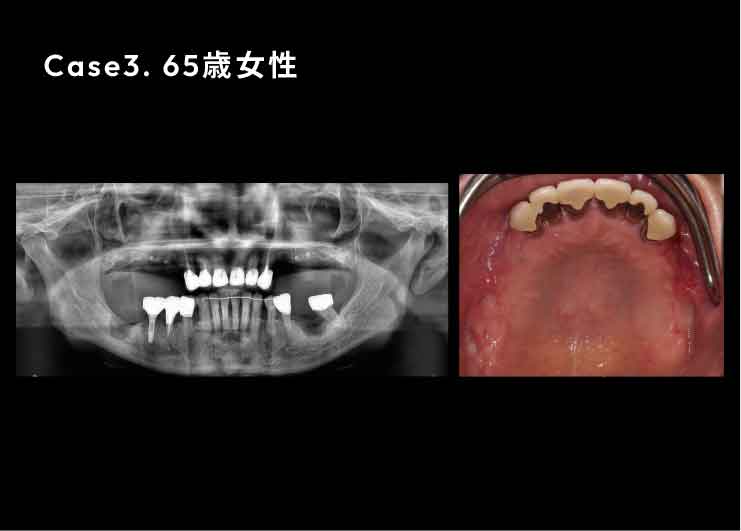

Case3. 65歳女性

歯周病でインプラント、歯が脱離。

上あごの骨が非常に薄く、そのままではインプラントを埋め込むことができないため、Xマークを使用したザイゴマ(頬骨)インプラントおよびプテリゴイド(蝶形骨)インプラントを行ったケース。

ザイゴマインプラント

上あごの骨が十分にない場合には、強固な頬骨に長めのインプラントを埋め込むことで、しっかりとインプラントを固定することができます。

X-ガイドにより、正確な手術が可能です。

プテリゴイド(蝶形骨)インプラント

骨移植など、サイナスリフトを避けた手術を行えます。X-ガイドにより、正確な手術が可能です。

インプラントでかみ合わせをしっかりと回復したことで、もともとあったほうれい線が術後には消えました。

奥歯でしっかりと噛めるようになることで飲み込む力が改善し、咳き込むことを防げるようになるほか、このように見た目も若々しくなっていきます。